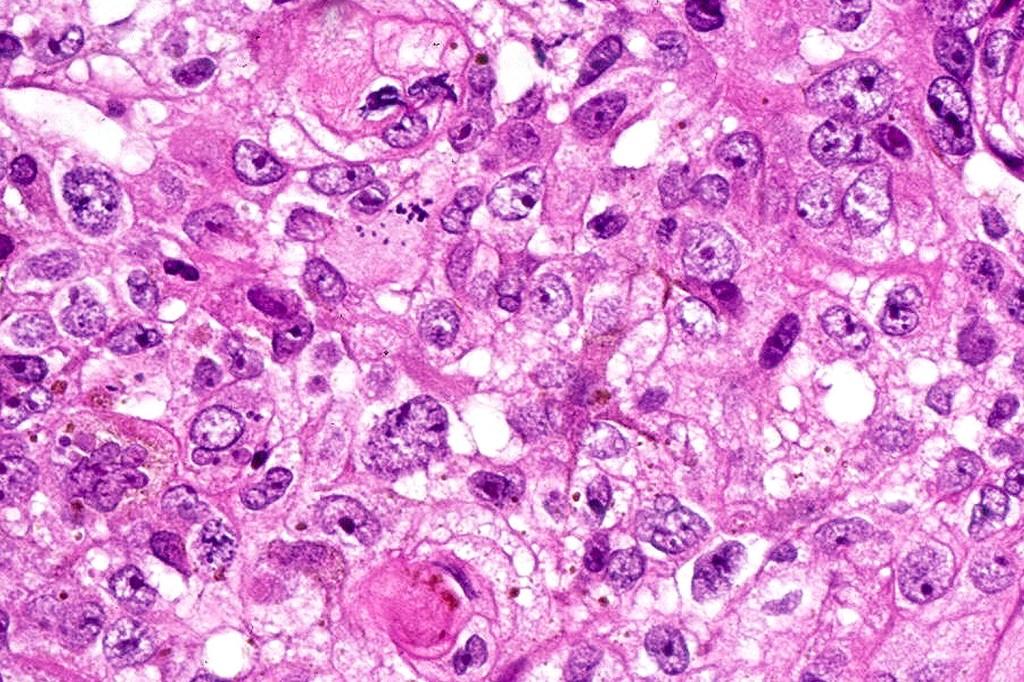

•Admixture of basaloid matrical, supramatricial & eosinophilic shadow cells with dendritic melanocytes. The ghost cell change is distinctive affecting individual cells with preservation of their cytological detail rather than the en masse change typical of pilomatricoma

•Variable pleomorphism and mitotic activity affecting the matrical cells